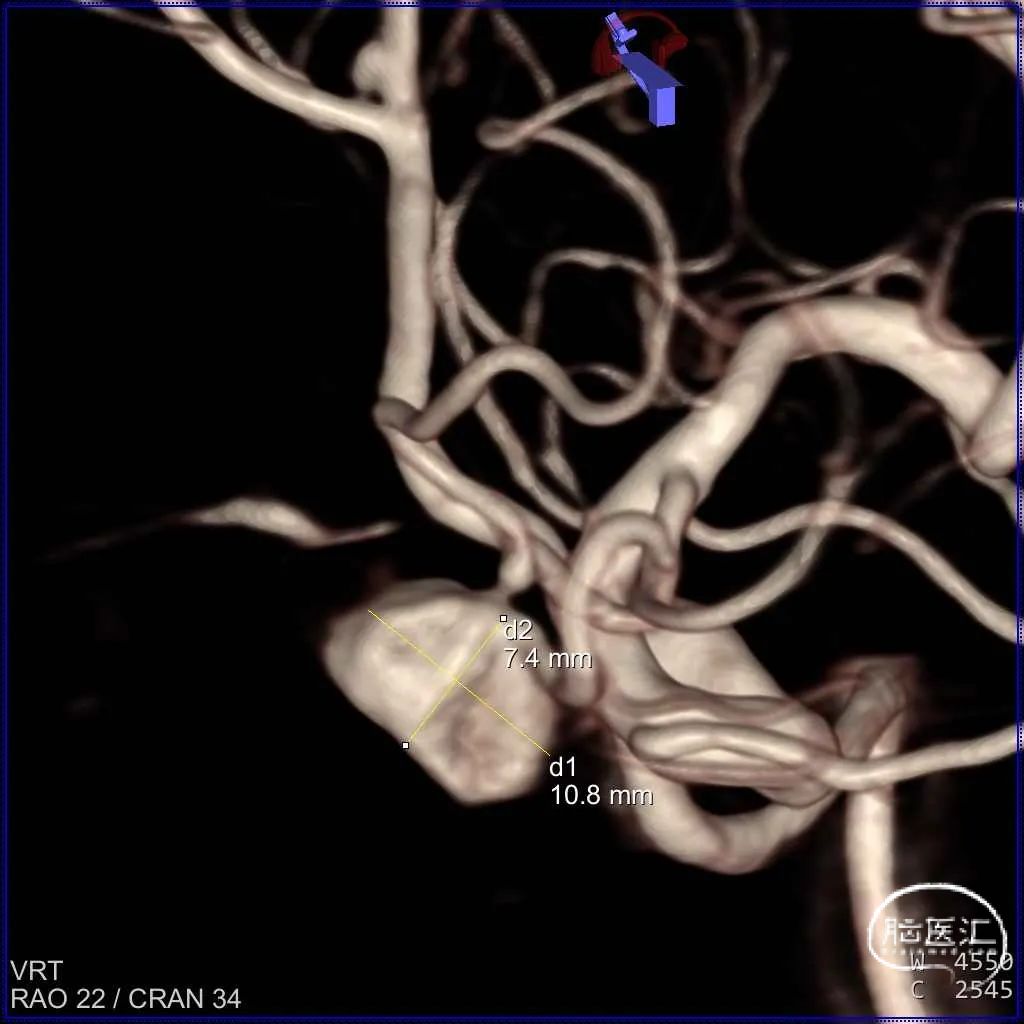

三维造影重建

三维重建测量瘤体、瘤颈及预估支架长度:

初步诊断:大脑前动脉动脉瘤。

位置:左侧大脑前动脉动脉瘤。

动脉瘤的形态:宽颈囊状,瘤内附壁血栓,造影可显影动脉瘤体积约为原始动脉瘤1/3。

动脉瘤大小(mm):长 10.8;宽 7.4;高 6.8

动脉瘤颈宽度(mm):3.7

载瘤动脉直径(mm):远端 1.1;近端 1.4